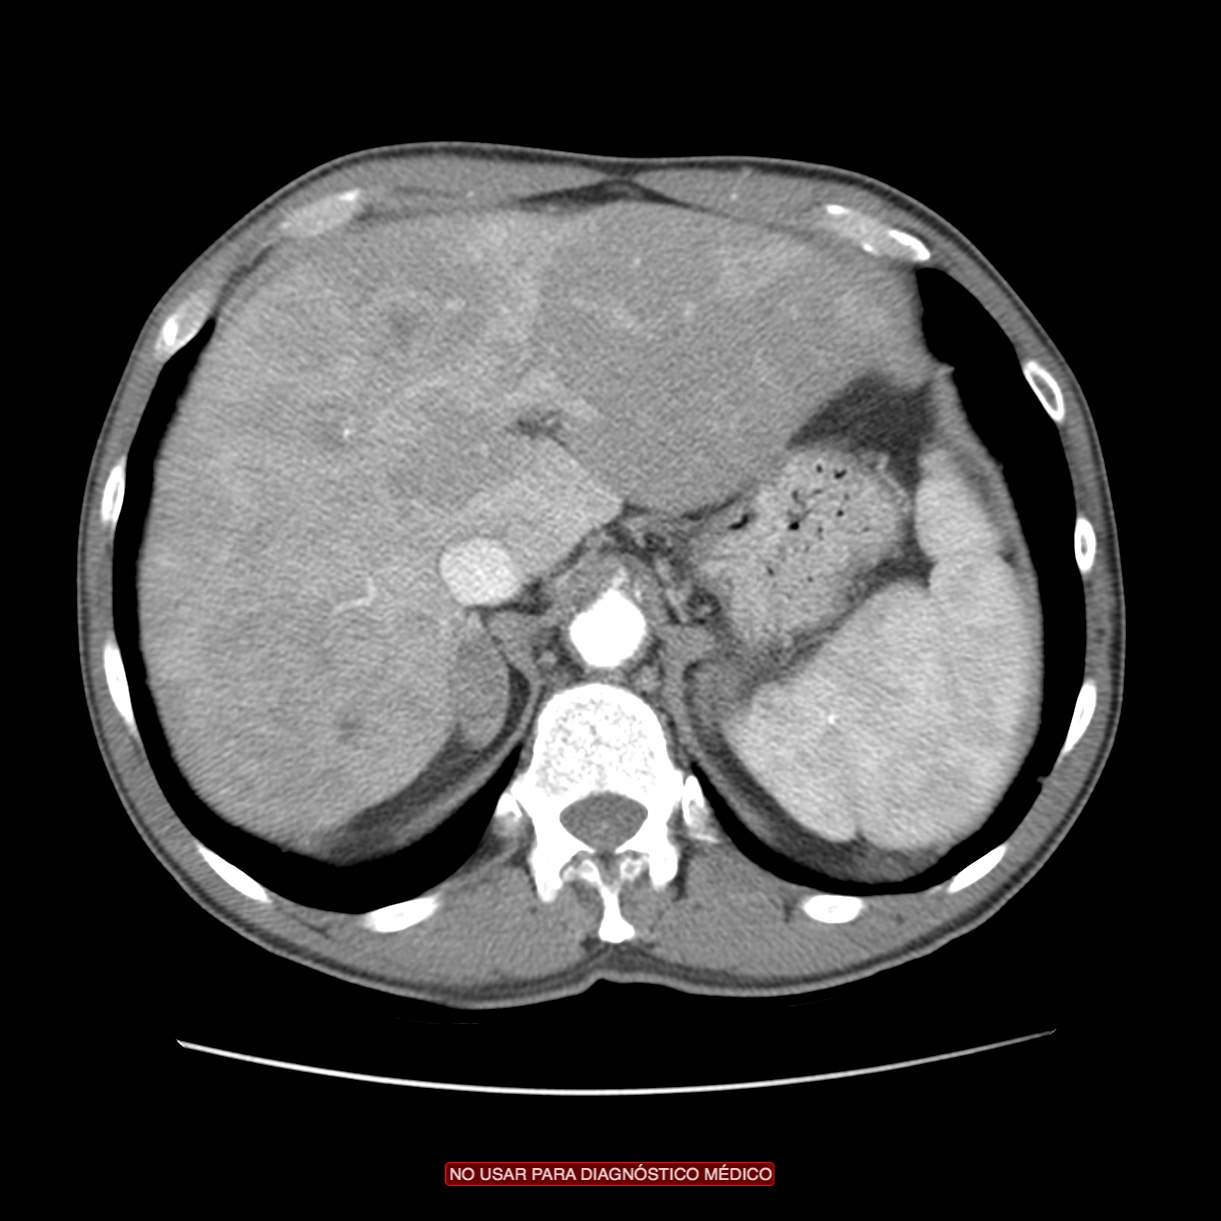

CASO CLÍNICO: Recopilatoción.

Paciente de 59 años con antecedentes personales de Cá de vejiga.

Se le realiza una Uro-Tc por seguimiento al año, aunque en esta ocasión el paciente refiere episodio de hematuria.

Tras el tratamiento de la recidiva y nefrostomía para la hidroureteronefrosis, vuelve acudir al hospital a los 9 meses por episodio de dolor en FD y malestar general. Se realiza una ecografía de urgencias.

Se realiza nueva TC bifásico abdominopélvio y Uro TC.

- Paciente con numerosas recidivas por Cá vejiga.

- Ha desarrollado un tumor metacrónico en pelvis renal derecha, también responsable de la hidroureteronefrosis.

- Mala evolución radiológica del proceso a expensas de metástasis pulmonares y hepáticas.